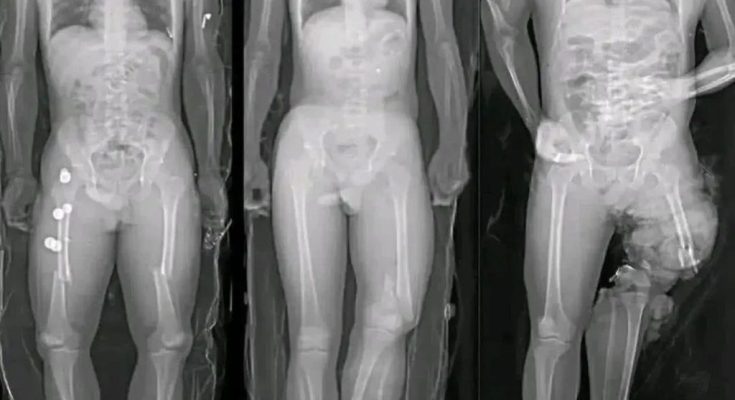

The success of these viral messages lies in how they are constructed. Fear-based imagery has always been effective at capturing attention, especially when combined with incomplete or vague warnings. A syringe aimed at a heart immediately suggests danger, even before a viewer reads any accompanying text. This technique taps into a natural instinct to protect oneself from harm.

Another reason these images resonate is that they exploit real but rare medical terms, such as myocarditis, without explaining scale or context. By presenting isolated facts without proportion, they create the illusion of widespread risk where none exists.